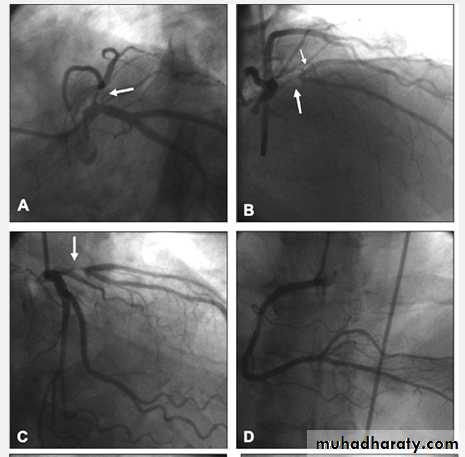

Proximal LAD PCI

Bifurcational lesion PCI